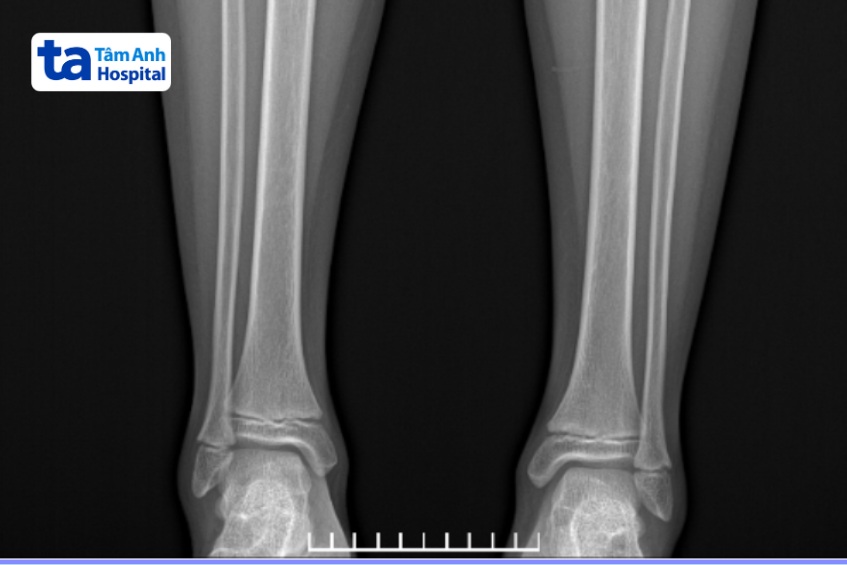

Chụp X quang là phương pháp tạo nên hình ảnh giải phẫu cấu trúc cơ thể một cách khá chi tiết bằng cách sử dụng tia bức xạ X. Đây là loại tia có khả năng đi xuyên qua và được các cơ quan trong cơ thể hấp thụ với mức độ khác nhau.

Dựa vào phim X quang, bác sĩ có thể quan sát, đánh giá về bộ phận cơ thể cần kiểm tra, chẩn đoán chính xác về sự tổn thương do chấn thương hoặc bệnh lý và đưa ra hướng điều trị phù hợp.

Bác sĩ có thể chỉ định trẻ em thực hiện chụp X quang trong các trường hợp sau đây: